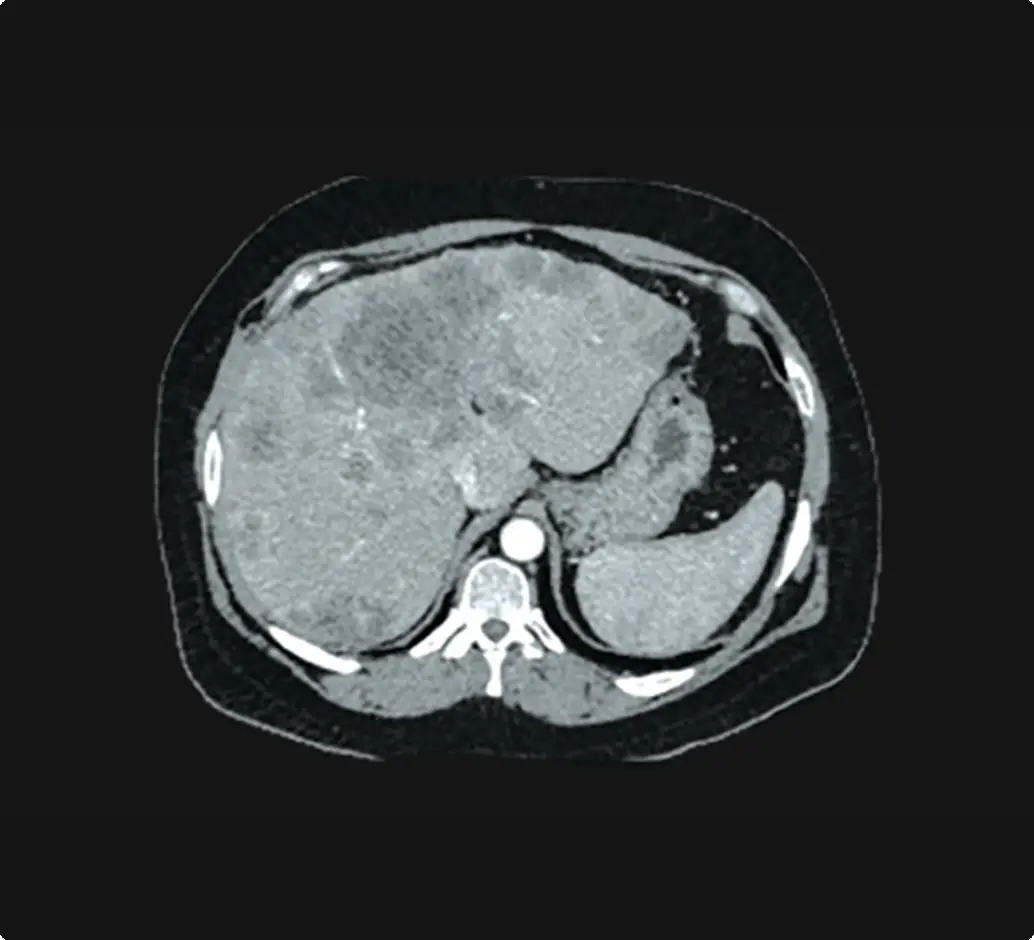

Protecting the liver is critical

In patients with borderline liver function, the approach must achieve a two-fold goal of effective treatment while preserving adequate healthy liver tissue.4 Elevated liver biomarkers are associated with poor prognosis in HCC.5